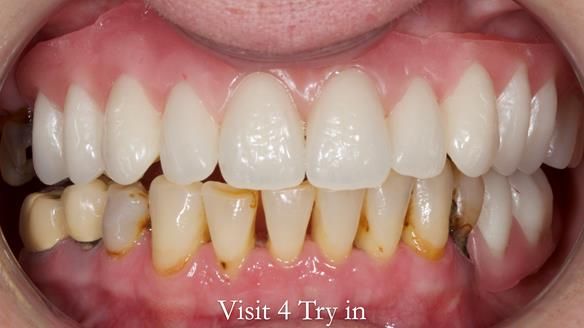

This newsletter describes the full protocol workflow of a complete upper denture and a lower partial denture for Jo.

“Hate the way the look. They do not 'work'... I cannot bite anything or chew properly. I cannot smile properly. My false teeth move and constantly need adhesive many times per day. They look false and give me a lisp when talking. In short, I just hate absolutely everything about my teeth at the moment.”

- “To have teeth (cf dentures) that I can eat and smile with”

- The forces placed on the teeth are large (bruxism). This will make the dentures proposed in the treatment plan below wear, chip and break more quickly. Therefore, the final dentures will require metal reinforcement to make them as robust as possible.

The clinical situation and treatment process is shown in detail below. I provided the clinical work. Rowan Garstang provided the technical work. This treatment took 25 visits over a period of 12 months.